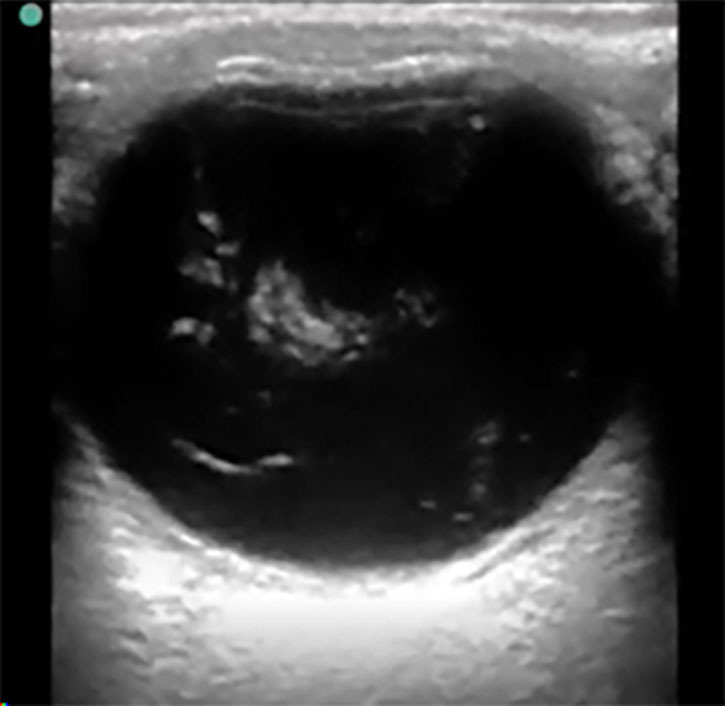

Additional methods of evaluating the posterior segment of the eye may include digital fundus photography and ultrasound. Digital fundus photography has been shown to have reasonable sensitivity and high specificity and can be interpreted remotely or asynchronously by an ophthalmologist, when linked into the electronic health record.33 A detailed fundoscopic exam can detect evidence of vascular disease, such as a Hollenhorst plaque, which can lead the clinician toward a diagnosis of amaurosis fugax secondary to ischemia. As mentioned earlier, POCUS has demonstrated high sensitivity and specificity for diagnosing retinal detachments and also can be used to evaluate for other ocular pathologies.30,34 Using POCUS, retinal detachments will appear as wavy lines tethered to the posterior segment of the eye. (See Figure 2.) Vitreous hemorrhages will display a sign called the “washing machine sign,” in which the echogenic blood will swirl when the globe is moved from side to side and typically is not tethered to the posterior segment. (See Figure 3.) To see an example of this, visit: https://emottawablog.com/2022/08/ocular-pocus-keep-your-prize-on-the-eyes/#:~:text=Vitreous%20hemorrhage%20occurs%20when%20extravasated,a%20“washing%20machine%20sign”.

Figure 3. Vitreous Hemorrhage |

![]() |

Ocular point-of-care ultrasound (POCUS), or B-scan, showing swirling hyperdense echogenic densities seen in vitreous hemorrhage Courtesy of Jodi Jones, MD |